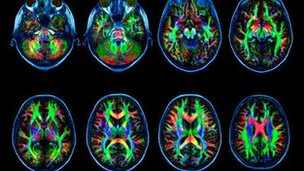

Las personas adictas a internet muestran cambios en el cerebro similares a los adictos a sustancias como drogas o alcohol, afirman investigadores en China.

El estudio llevó a cabo escáneres cerebrales en 17 jóvenes adictos a internet y encontró trastornos en las conexiones del cerebro.

En la investigación, los escáneres de imágenes de resonancia magnética (MRI) mostraron diferencias en los cerebros de los individuos con IAD.

Se observaron cambios en la materia blanca del cerebro, la parte del sistema nervioso central que contiene los axones, las fibras de las neuronas encargadas de conducir las señales nerviosas.

En particular, se encontró evidencia de trastornos en las conexiones en áreas del cerebro involucradas con las emociones, la toma de decisiones y el autocontrol.

¨En general, nuestros hallazgos indican que el IAD presenta anormalidades en la integridad de la materia blanca en las regiones cerebrales que involucran la generación y procesamiento de emociones, atención, toma de decisiones y control cognitivo¨, explica el doctor Hao Lei.